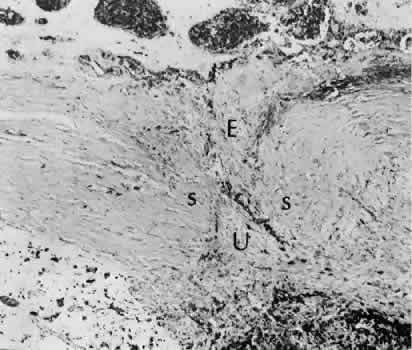

The sclera itself does not participate directly in wound healing. Partial-thickness injuries are healed by formation of granulation tissue from the epi-scleral tissue in external wounds or from uveal tissue in internal wounds (Fig. 8). Full-thickness defects of the sclera heal by granulation tissue originating in the episcleral tissue and uveal tract. Mitomycin is used in filtering procedures specifically to prevent the formation of granulation tissue and promote establishment of an aqueous fistula.30

Fig. 8. Following a scleral incision, granulation tissue from episcleral tissue (E) and uveal tissue (U) will proliferate through the full extent of the sclera. The tissue will remodel along tension lines to reapproximate the tensile strength of the original tissue (Hematoxylin-eosin stain; × 28.)